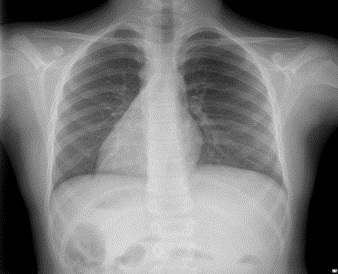

En el hospital se realiza un nuevo ECG, similar al anterior, y una radiografía de tórax (Fig. 2). En la exploración física se detectan tonos cardiacos en hemitórax derecho. Se realiza un ECG con electrodos en espejo (Fig. 3), que es normal.

Figura 2. Radiografía de tórax

Radiografía de tórax

Se realiza una ecografía clínica (urgencias), en la que se aprecia dextrocardia. Corazón normofuncionante, bien configurado, en posición especular. Hígado en el lado izquierdo, lóbulo derecho central. No se visualiza bazo. Riñones normales.

Diagnóstico: situs inversus.